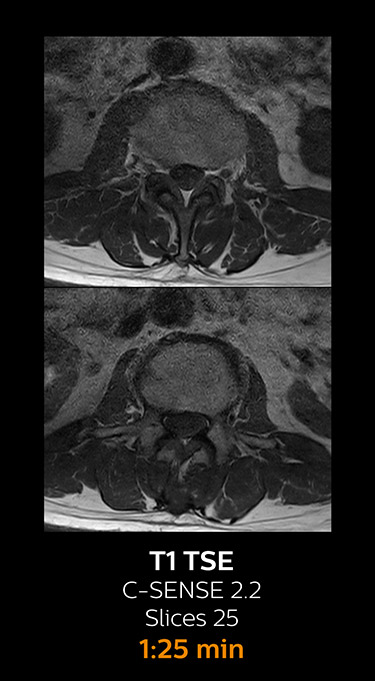

With Compressed SENSE, the scan time for the routine cervical spine examination at KNC was reduced from 13:11 to 9:52 minutes, which corresponds to 25% reduction.

MRI examination of the cervical spine with Compressed SENSE

Ingenia 3.0T CX

Scan time 9:52 min. (was 13:11 min. without Compressed SENSE)